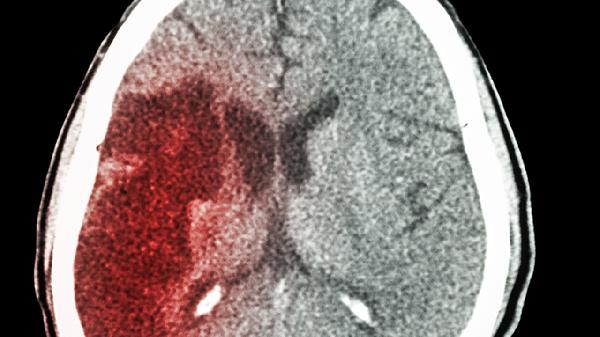

脑梗来临并非“静悄悄”,提醒:身体出现4种异常,或是脑梗前兆

脑梗就像个狡猾的小偷,总爱在人们毫无防备时突然袭.击。但再精明的罪犯也会留下蛛丝马迹,我们的身体其实早就发出了预警信号,只是很多人忽略了这些"求.救暗号"。